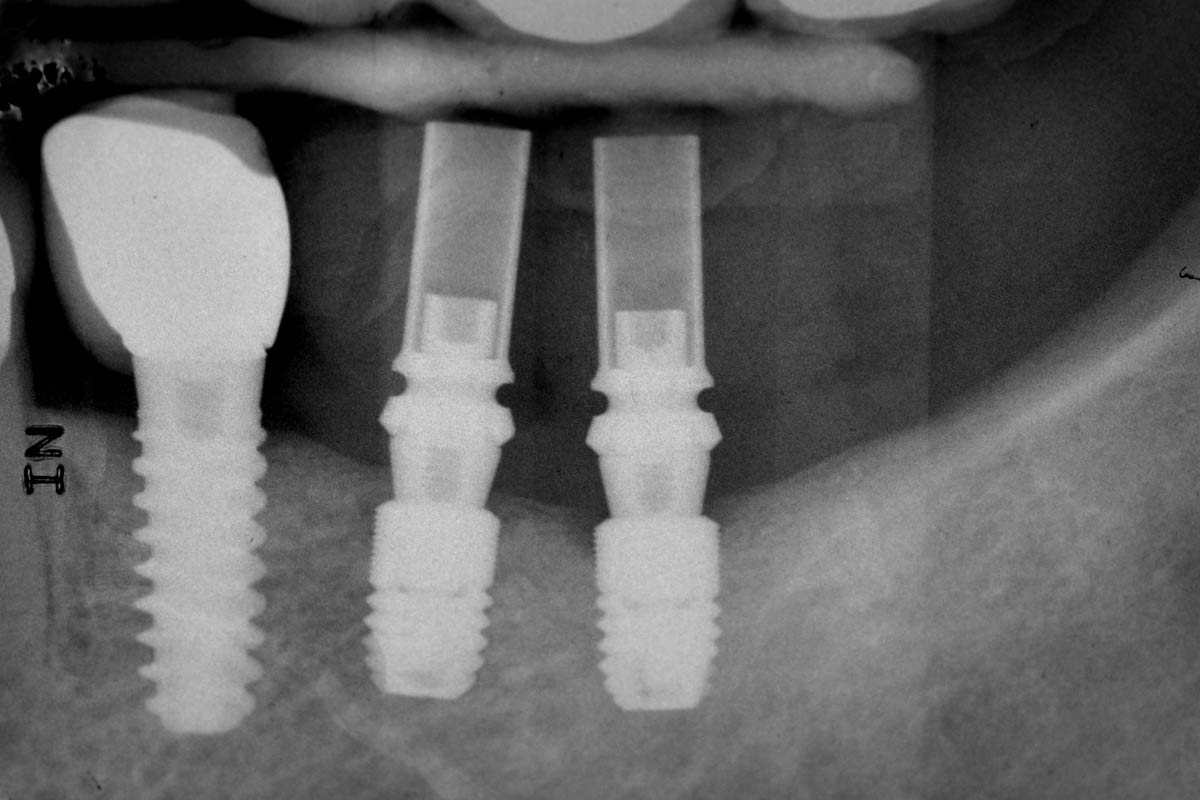

15/16 - Post-surgical x-rayPeri-implant soft tissue thickening with mucoderm® - Dr. F. Rojas-Vizcaya